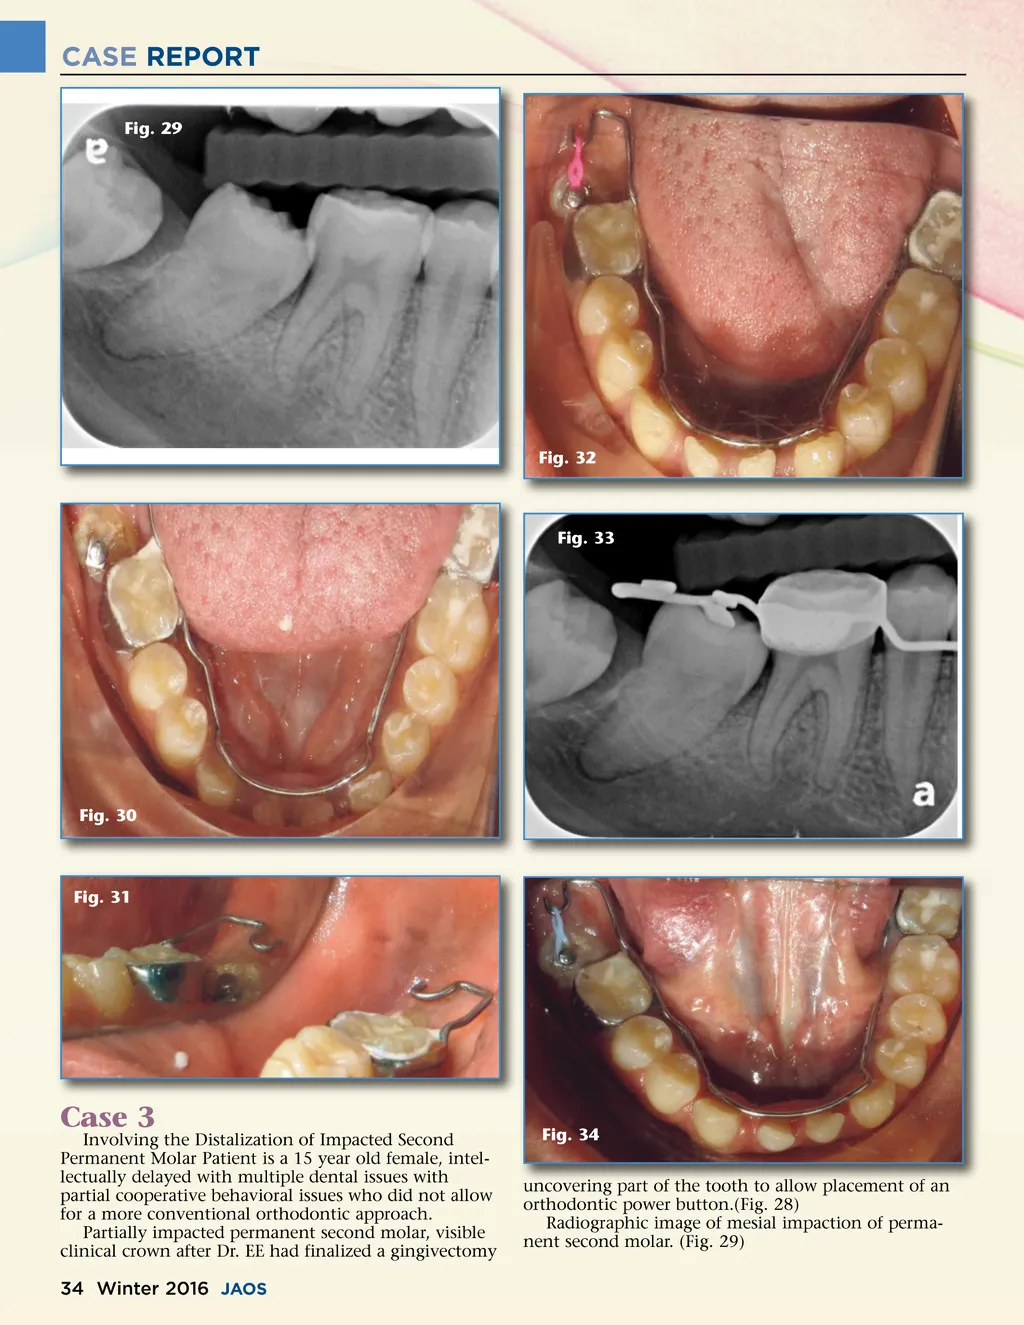

CASE REPORT Fig. 29 Fig. 32 Fig. 33 Fig. 30 Fig. 31 Case 3 Involving the Distalization of Impacted Second Permanent Molar Patient is a 15 year old female, intel-lectually delayed with multiple dental issues with partial cooperative behavioral issues who did not allow for a more conventional orthodontic approach. Partially impacted permanent second molar, visible clinical crown after Dr. EE had finalized a gingivectomy Fig. 34 uncovering part of the tooth to allow placement of an orthodontic power button.(Fig. 28) Radiographic image of mesial impaction of perma-nent second molar. (Fig. 29) 34 Winter 2016 JAOS